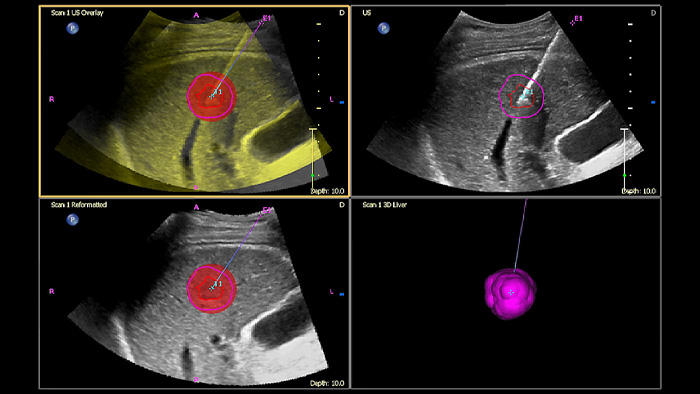

Make confident decisions even in challenging diagnostic cases with Philips image fusion and needle navigation capabilities. Streamlined workflow allows clinicians to achieve fast and effective fusion of CT/MR/PET with live ultrasound while needle navigation aids in guiding biopsy of small and difficult-to-access lesions2.

Using Tumor contour, users can plan and target lesions with a semi-automated tool that helps outline a 3D contour around a structure of interest, potentially improving procedure guidance with challenging cases where the lesion may not be easily visualized.